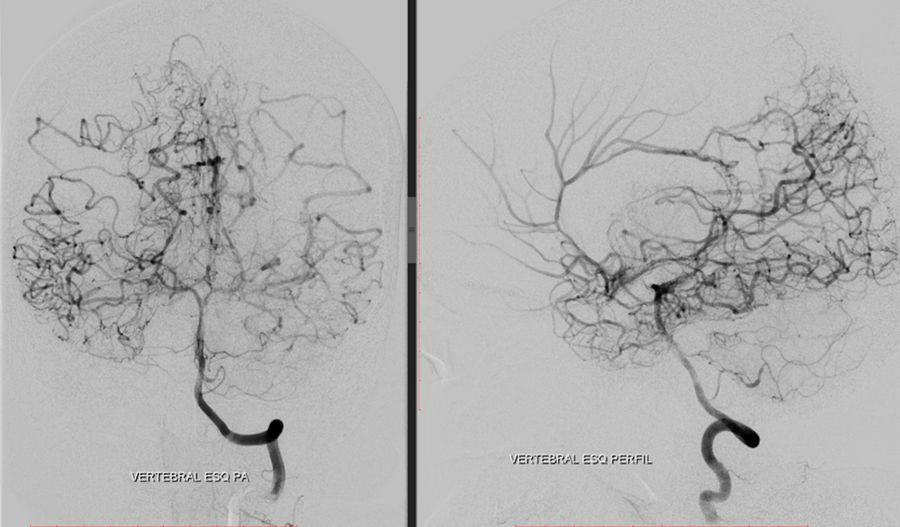

Catheter angiography was performed with the following findings:

• Occlusion at the proximal third of the cervical segment of the right internal carotid artery

• Stenosis of the supraclinoid segment of the left internal carotid artery

• Proximal stenosis of the anterior and middle cerebral arteries with collateral «smoke puff» vessels, which are characteristic findings of moyamoya disease

• Collateral circulation from the internal maxillary artery to the ipsilateral carotid territory

• Collateral irrigation of the carotid territory from the posterior circulation through a patent posterior communicating artery

A DSA (digital subtraction angiography) was performed pre-operatively to assess the occlusions of the internal and external

carotid arteries, as well as stenosis of the arteries and the feeding and draining blood vessels of the arteriovenous malformation, as

shown in the images below.